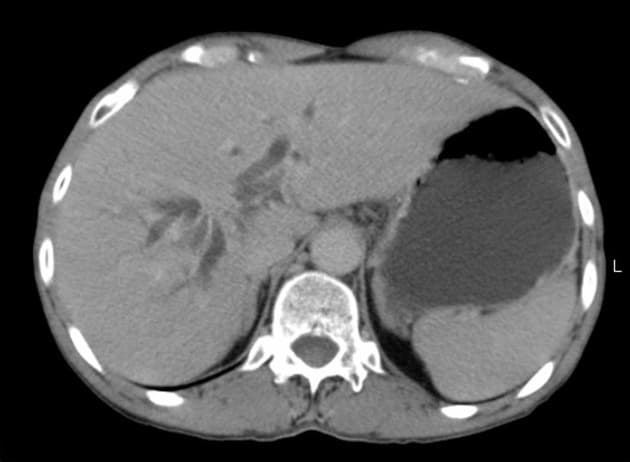

- Chụp cắt lớp ngang T2WI: thấy các ống mật trung tâm giãn khu trú, kết thúc tại một khối giảm tín hiệu ở vị trí nối các ống mật gan chính.

- T1 FS: tổn thương giảm tỷ trọng ở trung tâm, tại/gần cửa gan (porta hepatis). Không thấy tăng quang đáng kể sau tiêm thuốc cản quang.

Ung thư ống mật tế bào gan vùng cửa gan (hilar cholangiocarcinoma – u Klatskin) (hilar cholangiocarcinoma - Klatskin tumor).

Ung thư ống mật tế bào gan vùng cửa gan, còn gọi là u Klatskin, là khối u ác tính xuất phát từ biểu mô của các ống mật gần, đặc biệt tại vị trí nối ống mật gan phải và trái. Bệnh thường khởi phát âm thầm với các triệu chứng không đặc hiệu như vàng da, ngứa, sụt cân, gây khó khăn trong chẩn đoán. Trên hình ảnh, tổn thương điển hình là khối u vùng cửa gan gây giãn ống mật theo phân thùy, với dấu hiệu 'cắt cụt' trên chụp đường mật. MRCP rất nhạy trong việc xác định mức độ và phạm vi tắc mật. Trên MRI có tiêm thuốc, khối u thường giảm tín hiệu và tăng quang kém trên các dãy T1 và T2. Việc phân biệt với các đoạn hẹp lành tính, đặc biệt trong viêm đường mật xơ hóa tiên phát, có thể khó khăn và cần sinh thiết hoặc đánh giá nội soi. Chẩn đoán sớm rất quan trọng để xem xét cắt bỏ phẫu thuật hoặc ghép gan, mặc dù phần lớn các trường hợp khi chẩn đoán đã không còn khả năng cắt bỏ.